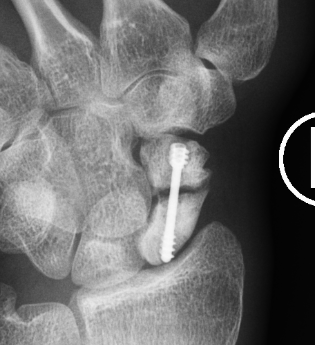

Post scaphoid ORIF

Xray

Nonunion with minimal displacement and minimal resorption

Nonunion with significant displacement and bone resorption

Proximal pole fracture with displacement and absorption